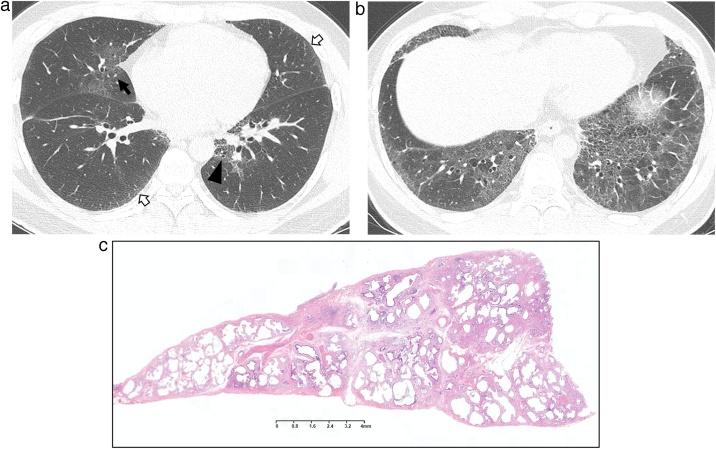

间质性肺异常(ILA)和非特异性间质性肺炎(NSIP)。

Interstitial lung abnormality (ILA) and nonspecific interstitial pneumonia (NSIP).

This review article aims to address mysteries existing between Interstitial Lung Abnormality (ILA) and Nonspecific Interstitial Pneumonia (NSIP). The concept and definition of ILA are based upon CT scans from multiple large-scale cohort studies, whereas the concept and definition of NSIP originally derived from pathology with evolution to multi-disciplinary diagnosis. NSIP is the diagnosis as Interstitial Lung Disease (ILD) with clinical significance, whereas only a part of subjects with ILA have clinically significant ILD. Eventually, both ILA and NSIP must be understood in the context of chronic fibrosing ILD and progressive ILD, which remains to be further investigated.

这篇综述文章旨在探讨间质性肺异常(ILA)和非特异性间质性肺炎(NSIP)之间存在的奥秘。ILA的概念和定义基于多项大规模队列研究的CT扫描结果,而NSIP的概念和定义最初源自病理学,并逐渐发展为多学科诊断。NSIP是具有临床意义的间质性肺疾病(ILD)诊断,而只有一部分ILA患者患有具有临床意义的ILD。最终,ILA和NSIP都必须在慢性纤维化ILD和进行性ILD的背景下理解,这仍有待进一步研究。